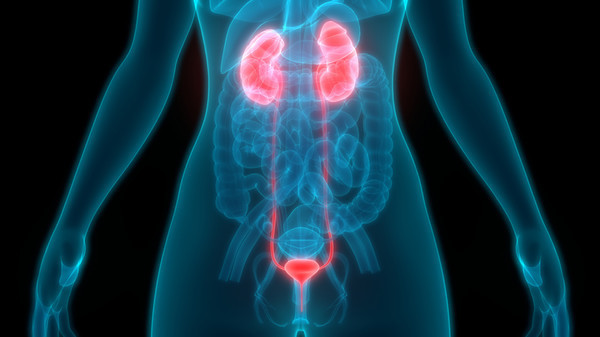

전립선암은 주로 전립선의 바깥쪽 부분인 말초대(Peripheral Zone)에서 발생합니다. 이 때문에 종양이 요도를 압박할 정도로 커지기 전까지는 증상이 나타나지 않는 경우가 많지만, 아래와 같은 비뇨기계 증상 및 전신 증상이 나타나기 시작하면 반드시 정밀 검사가 필요합니다.

- 설명: 암이 요도 주변이나 방광 쪽으로 침범하거나 전립선 내에서 출혈이 발생하면 소변에 피가 섞여 나오는 혈뇨가 발생할 수 있습니다. 혈뇨는 전립선암 외에도 방광암, 신장 질환 등 다양한 원인으로 발생할 수 있으므로, 육안으로 피가 보이거나 소변 검사에서 혈뇨가 확인되면 즉시 정밀 검사가 필요합니다.